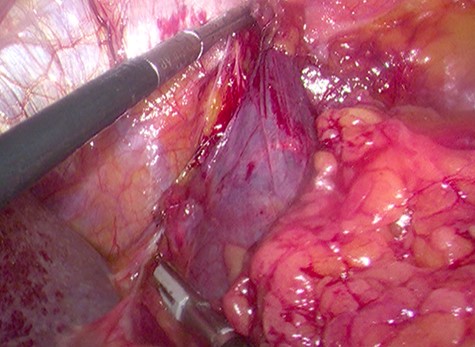

Because of its relatively large size and the patient’s request, he underwent a laparoscopic transperitoneal left adrenalectomy in the right lateral decubitus position (two 10-mm and one 5-mm ports). Intraoperatively, an enlarged left adrenal gland and a cystic lesion closely adherent to it were found, surrounded by adipose tissue (Figs 3 and 4). They were completely resected en bloc and removed in the endobag. No adverse events occurred postoperatively and he was discharged on Day 3.

Laparoscopic en bloc resection of the retroperitoneal cystic lesion adherent to the left adrenal gland and adipose tissue.